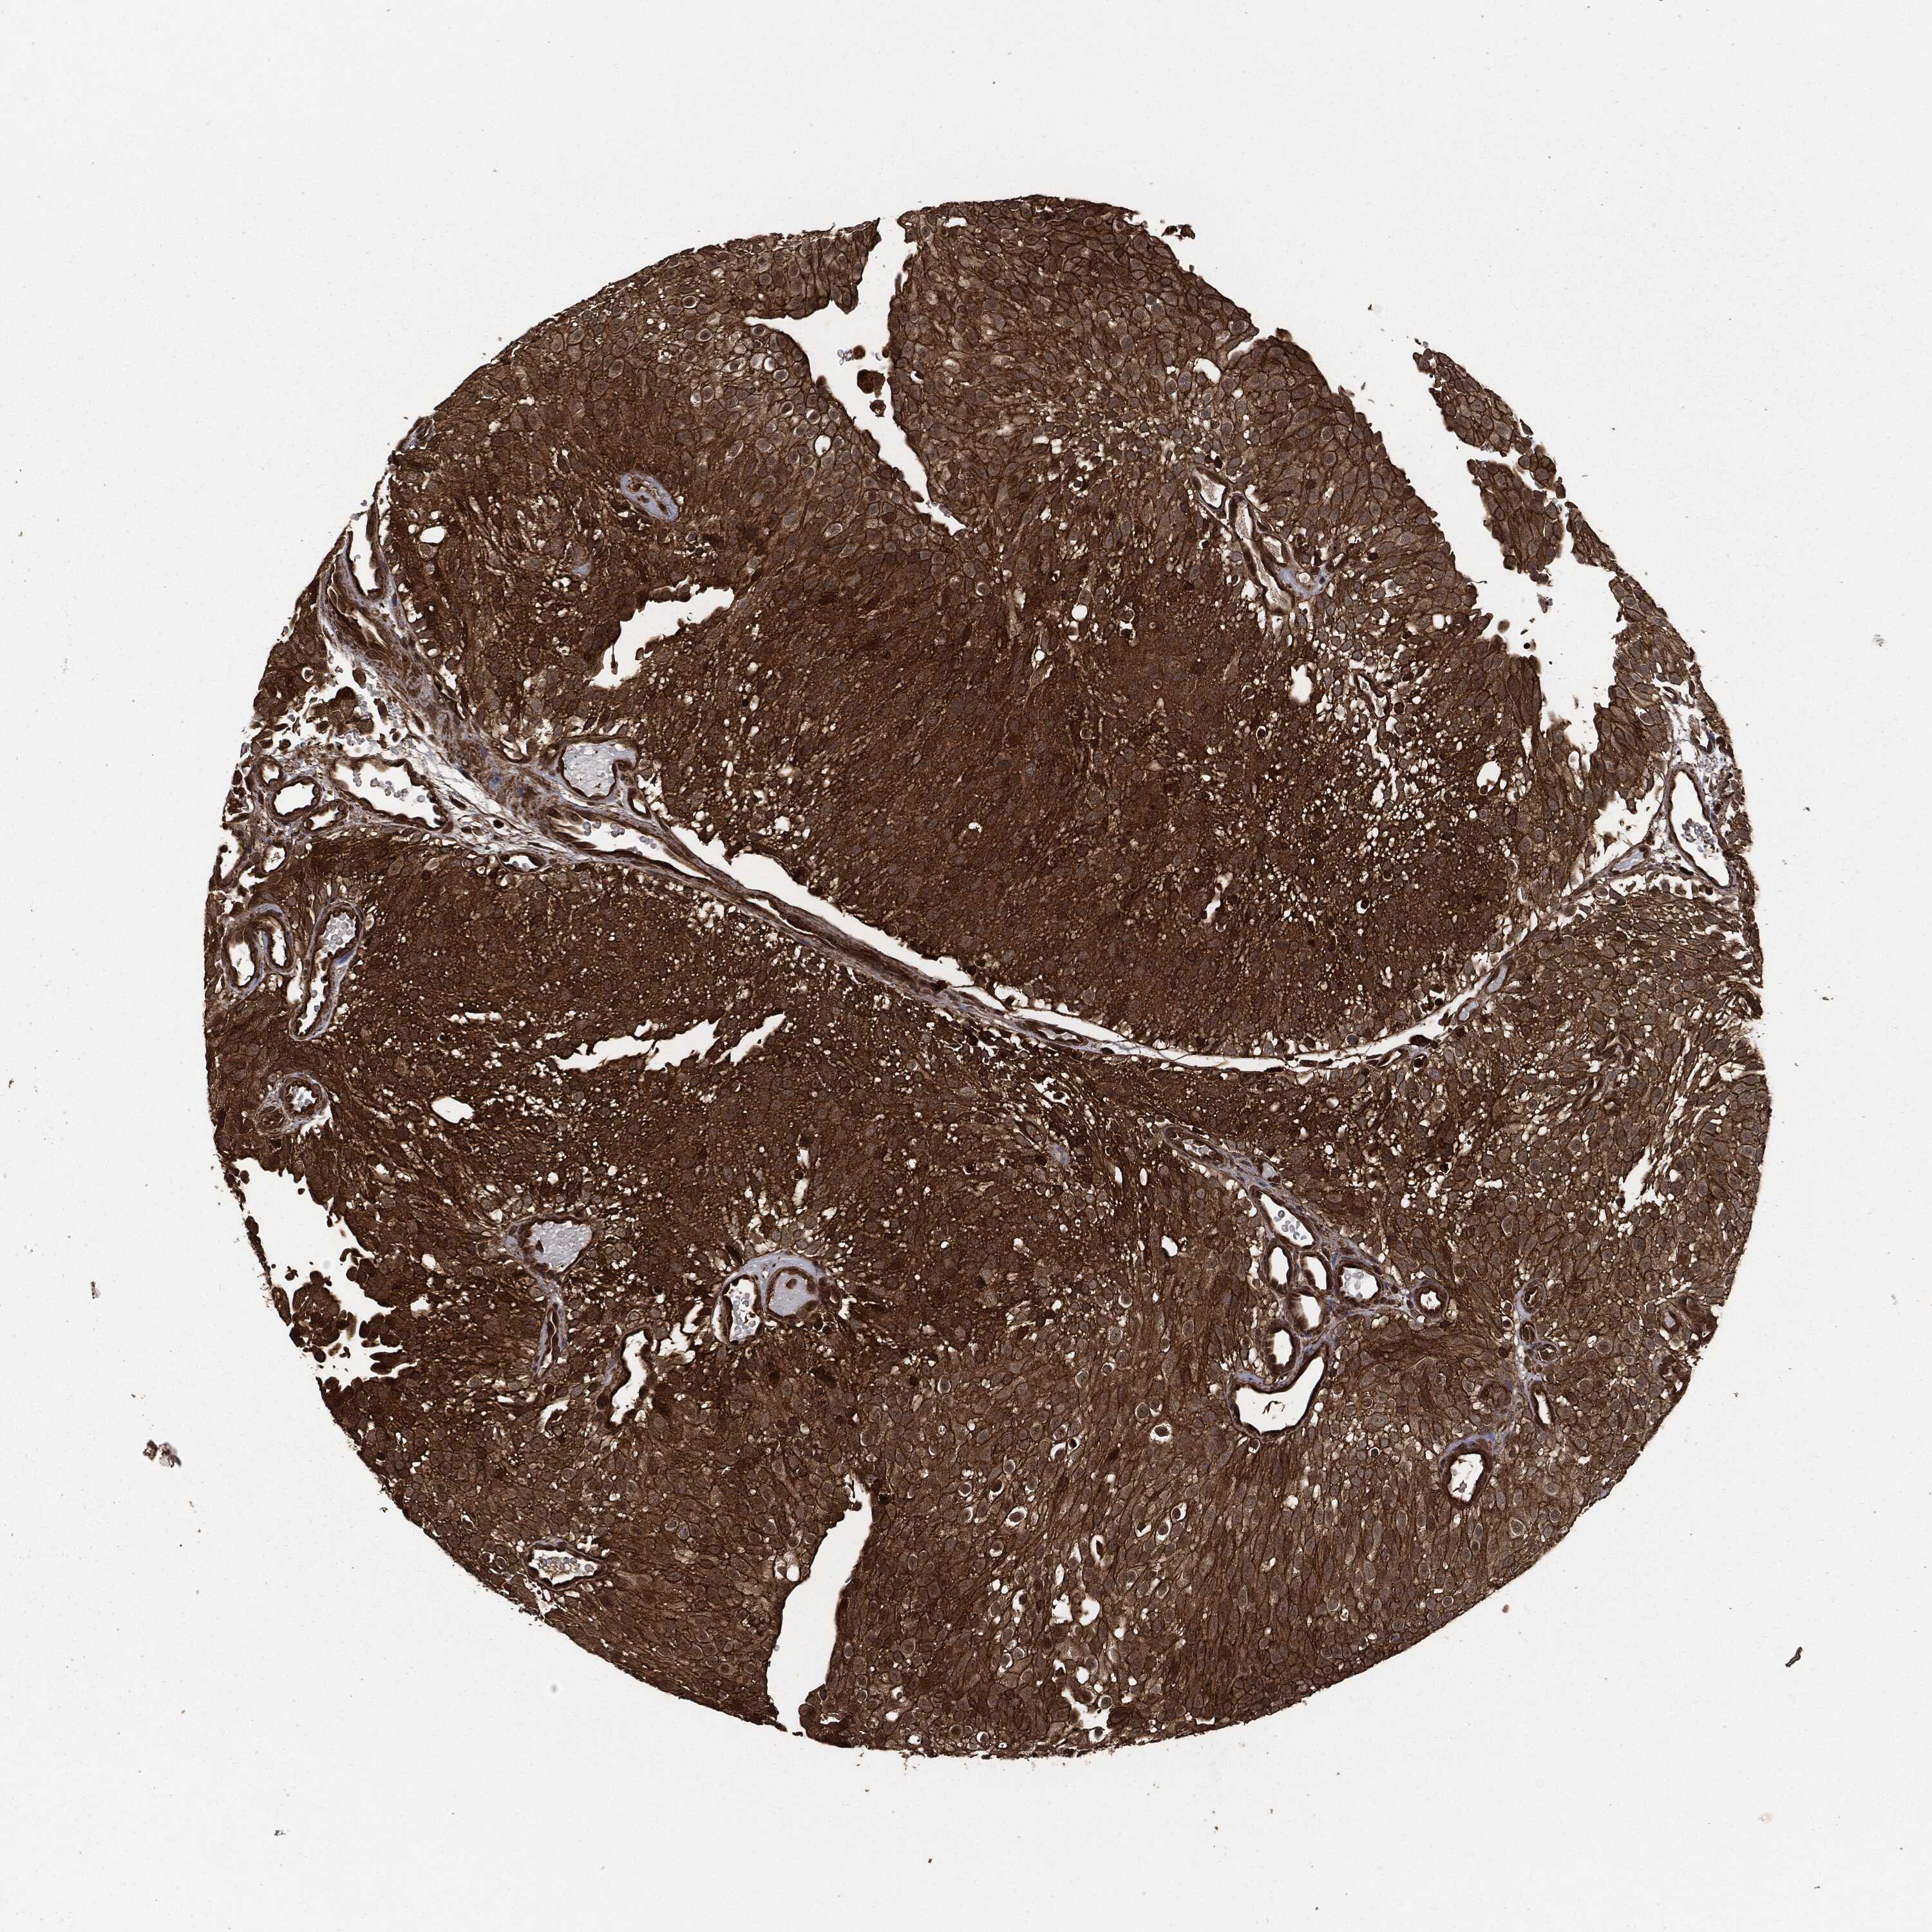

UROTHELIAL CANCER - Protein expressioni

A mouse-over function shows sample information and annotation data. Click on an image to view it in a full screen mode. Samples can be filtered based on level of antibody staining by selecting one or several of the following categories: high, medium, low and not detected. The assay and annotation is described here.

Note that samples used for immunohistochemistry by the Human Protein Atlas do not correspond to samples in the TCGA dataset.

Antibody stainingi

Antibody staining in the annotated cell types in the current human tissue is reported as not detected, low, medium, or high, based on conventional immunohistochemistry profiling in selected tissues. This score is based on the combination of the staining intensity and fraction of stained cells.

Each image is clickable and will lead to virtual microscopy that enables deeper exploration of all samples and also displays staining intensity scores, fraction scores and subcellular localization as well as patient and tissue information for each sample.

CAB080330

Urothelial carcinoma, High grade

Urothelial carcinoma, NOS

Urothelial carcinoma, Low grade

Adenocarcinoma, NOS